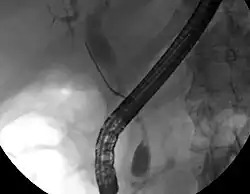

Wiewohl die Bildgebung der Oberbauchorgane für die Diagnose des Gallengangskarzinoms hilfreich sein kann, ist eine Darstellung der Gallenwege mit einem Kontrastmittel oft unumgänglich. Zu diesem Zweck wird die Endoskopisch retrograde Cholangiopankreatikographie (ERCP), ein endoskopisches Verfahren als Mittel der Wahl von Gastroenterologen oder Chirurgen eingesetzt. Obwohl die ERCP eine invasive Maßnahme mit allen damit verbundenen Risiken ist, bestehen ihre Vorteile doch darin, dass Gewebeproben zur Diagnose entnommen und ein röhrenförmiges Implantat in den Gallengang eingesetzt werden kann, um dadurch die Verlegung der Gallenwege zu beseitigen.[38]

Während der ERCP kann ein endoskopischer Ultraschall durchgeführt werden, um die Entnahme von Gewebeproben mittels Biopsie zu vereinfachen. Außerdem können so ein möglicher Lymphknotenbefall besser beurteilt und Informationen zur Frage der Operabilität des Tumors gewonnen werden.[46] Alternativ zur ERCP kann die Perkutane transhepatische Cholangiographie (PTC) eingesetzt werden. Die Magnetresonanz-Cholangiopankreatikographie (MRCP) ist eine nicht-invasive diagnostische Alternative zur ERCP.[47][48][49] Einige Autoren haben vorgeschlagen, in der Diagnostik bei biliären Tumoren die ERCP generell durch die MRCP zu ersetzen, da auch so der Tumor diagnostiziert werden kann und die Risiken der ERCP vermieden werden.[50][51][52]